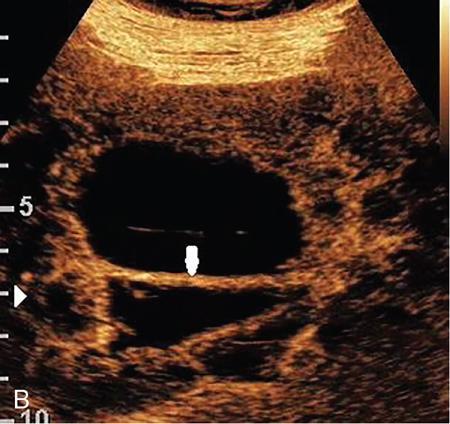

Drushi Patel CONTRAST-ENHANCED ULTRASOUND IN ADULT GENITOURINARY IMAGING Mridula Muthe Ultrasound is the initial screening examination for the evaluation of the renal morphology and suspected renal lesions due to its multiple advantages such as easy accessibility, bedside assessment, affordability and lack of radiation. Vascularity of the kidney and renal lesions can be studied with the use of colour Doppler ultrasound however, it provides information only about the macrovasculature. With the use of microbubble ultrasound contrast agents (UCAs) macro as well as the microvasculature can be studied. Contrast-enhanced ultrasonography (CEUS) is also more sensitive than Doppler ultrasound as it is not affected by blood velocity and angle of insonation of the ultrasound beam. In urology, the established applications of CEUS in adults include characterization of cystic lesions and differentiation between pseudotumours and solid lesions. Box 10.23.1.1 provides a list of European Federation of Societies for Ultrasound in Medicine and Biology (EFSUMB) recommended indications of CEUS in renal evaluation. EUROPEAN FEDERATION OF SOCIETIES FOR ULTRASOUND IN MEDICINE AND BIOLOGY (EFSUMB) RECOMMENDED INDICATIONS FOR USE OF UCA IN RENAL EVALUATION Renal ischaemia. Evaluation of solid renal lesions. Differentiation between solid renal lesions and pseudotumours. Characterization of complex cystic masses. Characterisation of indeterminate renal masses. Renal infections. Follow-up of nonsurgical complex masses. To improve lesion visualization in patients undergoing renal tumour ablation under US guidance and to detect residual tumour either immediately or after ablation. Isolated blunt moderate-energy renal trauma. Follow-up of trauma patients managed conservatively. Characterization of thrombus in renal vein and inferior vena cava. In patients with contraindications for CT- and MRI-based contrast media. Evaluation of lesions in transplant kidneys. Evaluation of ischaemia and vascular complications in transplant kidneys. Tumour response assessment to biologic therapy. Intracavitary CEUS for guiding percutaneous nephrostomy. Source: P.S. Sidhu, V. Cantisani, C.F. Dietrich, O.H. Gilja, A. Saftoiu, E. Bartels, et al., The EFSUMB guidelines and recommendations for the clinical practice of contrast-enhanced ultrasound (CEUS) in non-hepatic applications: update 2017 (long version). Ultraschall in der Medizin-Eur. J. Ultrasound 39 (02) (2018) e2–e44. CEUS involves the intravenous injection of UCAs consisting of gas microbubbles. These UCAs remain purely in the intravascular compartment as they are small enough to avoid filtration by the lungs and too large to enter the interstitial compartment. UCAs cause marked amplification of signals from the flowing blood, thus providing information about the microvasculature and parenchymal perfusion. Sonovue is a second-generation UCA and is the only UCA available in India. It consists of sulphur hexafluoride gas which is exhaled by the lungs and is surrounded by phospholipid monolayer which is metabolised by the liver, making it safe for patients with renal insufficiency. For renal evaluation, a dose of 1–1.5 mL of Sonovue is administered as a bolus dose followed by a 10 mL saline flush. CEUS is performed on machines with contrast-specific software’s using a low mechanical index (MI) technique. The use of a dual image display is beneficial for the evaluation of small lesions. A conventional B-mode ultrasound is first performed to acquire measurements, assess morphology and to detect focal lesions along with Doppler ultrasound to assess vasculature. However, due to limitations in the assessment of focal lesions, microvasculature, complex cysts, poor contrast between the lesion and cortex or medulla, it is preferable to perform a CEUS study for additional characterization. The enhancement pattern of the kidney is different than that of the liver due to the dual blood supply of the liver as opposed to afferent arterial supply and efferent venous drainage of the kidney. After an intravenous bolus of UCA, kidneys show intense enhancement. Contrast is first seen in the main renal artery, followed by its branches. CEUS has only two enhancement phases, that is cortical phase which lasts for 15–30 seconds and a parenchymal phase (enhancement of both cortex and medulla) for 25 seconds–4 minutes after UCA administration. The renal cortex enhances first, followed by the outer medulla which is followed by gradual enhancement of the pyramids (Fig. 10.23.1.1). During the washout phase first, there is a reduction in the medullary enhancement followed by a slower washout of the cortex. As kidneys don’t excrete UCAs, there is no opacification of the pelvicalyceal system. UCAs can act as a problem-solving tool in patients with renal failure as they are not nephrotoxic. Due to its excellent ability to depict renal vascularization, it can be used for detecting perfusion abnormalities. CEUS is useful for detecting vascular causes of renal function deterioration. Renal infarcts appear as wedge-shaped nonenhancing areas in all phases. Renal infarcts show a focal complete lack of parenchymal enhancement on CEUS whereas ischaemic areas show reduced enhancement. CEUS can confidently differentiate infarction from cortical necrosis by the demonstration of preserved hilar vascularity in the latter. Renal pseudotumours such as foetal lobulations, dromedary hump, parenchymal hypertrophy due to renal scarring and column of Bertini can be accurately differentiated from true tumours using CEUS. Pseudotumours show similar enhancement to the adjacent parenchyma and appear isoechoic on all phases while true tumours show different enhancement pattern on at least one phase (Fig. 10.23.1.2). True tumours will cause mass effect and distort the normal vascular architecture of the renal parenchyma whereas in pseudotumours the vascular architecture is preserved. In addition, the identification of medullary pyramids within the mass points towards it being a pseudotumour rather than a true mass. Cysts can be categorized according to the Bosniak classification using CEUS. Due to its superior spatial and temporal resolution, CEUS is considered superior to CT for detecting additional septations, wall or septal thickening and solid components (Figs 10.23.1.3–10.23.1.5). CEUS allows for real-time imaging of blood flow within the septae, wall or nodules within the cysts which may not be seen on CT or MR imaging. The sensitivity of CEUS is comparable to CT for the classification of renal cystic lesions as benign or malignant however, it is not as useful for staging. The follow-up of inoperable complex cystic lesions is better performed with CEUS rather than CT due to the absence of ionizing radiation. Complex cysts or masses with calcifications are not suitable for evaluation with CEUS. CEUS allows a detailed evaluation of the circulation in mass lesions as it demonstrates the macro as well as microvascular enhancement patterns. CEUS has more sensitivity than CT for detecting blood flow in hypovascular lesions. It can also be used to distinguish between complex cysts and solid lesions which remain equivocal on CT and ultrasound (B-mode and colour Doppler). CEUS is sensitive in identifying cystic areas, necrosis, debris and haemorrhage in small tumours that may be difficult to visualize on CECT and MR. Isoechoic lesions on conventional ultrasound are better characterized by CEUS (Fig. 10.23.1.6). Hyperdense renal lesions on noncontrast CT (NCCT) with HU values between 20 and 70 are better evaluated by CEUS which can classify these lesions as solid or cystic. CEUS can suggest the histological subtype of tumours. Clear cell carcinomas show heterogeneous hyperenhancement in the cortical phase and rapid washout along with a peripheral enhancing rim or pseudocapsule seen during the parenchymal phase. Papillary carcinoma shows progressive heterogeneous enhancement during the cortical phase and displays hypoenhancement as compared to the cortex on all phases. Malignant renal vein thrombus will show enhancement as compared to bland thrombus on CEUS. Tumours that are smaller than 3 cm commonly show homogeneous enhancement, regardless of their histologic subtype. Differentiation between angiomyolipoma, renal cell carcinoma and oncocytoma is not always possible. Although, CEUS has excellent sensitivity for the detection of malignancy, it has a higher false-positive rate as compared to CECT. Hence, combined use of CEUS for its high sensitivity and CECT for its high specificity may be performed for an accurate diagnosis. CEUS is effective in patients with complicated pyelonephritis, for identifying inflammatory parenchymal involvement, characterized by round or wedge-shaped hypovascular parenchymal areas, most conspicuous during the late parenchymal enhancement phase. An abscess is seen as a nonenhancing area, with or without peripheral or septal enhancement. CEUS can also be used for the follow-up of renal abscesses. All the aforementioned indications of CEUS in native kidneys also apply to renal transplants. Infarction, vascular complications such as arterial and venous thrombosis can be detected. Quantitative CEUS for assessment of graft dysfunction is a subject of active research. CEUS can be used as an alternative to CT especially in children with isolated blunt moderate energy injuries who are hemodynamically stable. It can also be used in the follow-up of conservatively managed trauma patients and in renal impairment. During Focused Assessment with Sonography for Trauma (FAST), the examination should begin with the kidneys as they have a fleeting enhancement. The kidneys are studied in the arterial phase with two separate doses administered for either kidney during FAST. On CEUS, lacerations, hematomas, and infarcts are seen as nonenhancing areas on late-phase images whereas contusions may show faint enhancement. Pseudoaneurysms and active bleeding are diagnosed on the arterial phase. Crucial complications such as devascularized parenchyma and acute cortical necrosis can also be diagnosed on CEUS. Pelvicalyceal system injury cannot be detected by CEUS as UCAs are not excreted by the kidneys. CEUS can be performed in conjunction with percutaneous ablation therapies. Preablation evaluation with CEUS is essential to assess lesion vascularity and to compare pre and postprocedure tumour viability. Also, the identification of a pseudocapsule predicts improved ablation efficacy. CEUS has demonstrated high sensitivity, specificity and accuracy for the early detection of residual unablated tumour. Dynamic contrast-enhanced ultrasound is a useful tool for early identification of responders and nonresponders, enabling tailoring of the treatment regimen. It is performed by two methods – Bolus injection of a UCA with time-intensity curve analysis (commonly used) and intravenous injection of UCA with disruption–replenishment analysis. In patients with chronic kidney disease, the contrast enhancement is less intense and fades earlier as compared to a normal kidney. CEUS aids in characterizing renal lesions in patients with renal failure. Characterization of lesions with indeterminate appearances in patients with renal dysfunction, on conventional US prevents unnecessary further evaluation with contrast-enhanced CT or MRI and further deterioration of the renal function as well as unwarranted investigations. CEUS nephrostomogram can be performed after percutaneous nephrostomography to confirm the correct positioning of its tip, detect the site of obstruction and to diagnose complications. UCAs can be safely administered in patients with minimal risk. They can be safely administered in patients with renal insufficiency as they are not excreted by the kidneys. Prior laboratory tests are not indicated as they are not nephrotoxic and don’t interact with thyroid function. Most adverse effects are mild such as nausea, headache, chest discomfort, chest pain and resolve spontaneously. The contraindications include known hypersensitivity, patients with right-to-left shunts, severe pulmonary arterial hypertension (pulmonary arterial pressure >90 mm Hg), uncontrolled systemic hypertension, and respiratory distress. The rate of anaphylactic reactions is significantly lower than iodinated contrast media and comparable to gadolinium-based contrast agents. Caution should be exercised in patients with severe acute coronary disease and in patients with unstable angina. CEUS is a rapidly evolving technique, can be conveniently performed as an extension of conventional ultrasound and acts as a valuable tool in the characterization of indeterminate renal lesions, especially when the lesion is small. The advantages of CEUS include quick assessment, real-time imaging, high contrast resolution, excellent safety profile, lack of ionizing radiation, great repeatability, and most importantly, ideal for contrast evaluation in patients with deranged renal function. DUAL-ENERGY AND SPECTRAL IMAGING IN GENITOURINARY SYSTEM Aditi Chaitanya Gujarathi-Saraf Dual-energy CT (DECT) also known as ‘spectral imaging’, was first conceptualized in the 1970s. However, the clinical applications of DECT have recently emerged as owing to improvements in postprocessing techniques. The development of a single-detector, single-source DECT (ssDECT) with the capability for rapid alternation between two peak voltage settings (‘fast switching’) and a dual-detector, dual-source DECT (dsDECT) system in last few years have made possible various applications in solving clinical problems. In DECT, the simultaneous use of two different X-ray beam energy settings (80 and 140 kVp) allows the differentiation of materials on the basis of their attenuation characteristics (material density). There are two major applications of DECT in genitourinary system. First being characterization of renal calculi to differentiate those containing uric acid (UA) from those which do not. The other application is to characterize small renal masses which include differentiating complex cysts from renal tumours, detection of solid growth in PCKD patients and detection of residual tumour after thermal ablation of a renal neoplasm. The principle of DECT imaging is based on the differential absorption of X-ray energy at variable kVp settings. In DECT, two energy levels (typically 80 and 140 kVp) are used to acquire images that can be processed to generate additional datasets. Thus, a tissue or any material in the body shows different degrees of attenuation when scanned at different X-ray energies. Conventional CT numbers (attenuation measurements in Hounsfield units) are related to the linear attenuation coefficient of a particular material. The unique linear attenuation coefficients obtained by imaging at two different energies can be used to discriminate between different materials (e.g. fat, calcium, iodine and water). The characterization of material on DECT depends on their CT number ratio (CTR) also called dual-energy ratio. DE RATIO = CT number of a given material in the low-energy image CT number of the same material in the high-energy image DECT and spectral CT can be performed by three techniques (Fig. 10.23.2.1): Two sets of material-specific images are created to detect the presence or absence of a material. The two basic materials selected should have significant difference in mass attenuation coefficients and atomic number. The two commonly selected pairs are: Iodine-specific images are most commonly used in the clinical practice. When iodine is paired with water, two separate image data sets are generated. On water density image, the voxels that show change in attenuation due to presence of iodine are removed. These are instead represented on iodine density images. Thus, virtual unenhanced images are generated which resemble the conventional unenhanced images. Renal calculus disease is a common disease affecting approximately 10%–14% of population in India commonly affecting 31–45-year-old patients. Accurate diagnosis of composition of renal calculi is crucial as the frequency of prevalence and recurrence rate of renal calculi is high in most states of India. The obstructing calculi can lead to obstructive uropathy, pyelonephritis, urinary sepsis with nearly 50% of the patients being affected by renal failure. There are multiple compositions of renal calculi, most common being calcium oxalate (70%), calcium phosphate (20%), uric acid (8%) and cystine (2%). In general, UA calculi have lower attenuation values than nonuric acid calculi (i.e. struvite, cystine and calcium) on conventional CT. However, it may be difficult to distinguish between the two due to overlap in attenuation values. Here DECT becomes a problem-solving tool as it uses the two-material differentiation approach. Thus, in addition to size and location, DECT provides information about the composition of calculi to the urologist. DECT has high sensitivity of 88%–100% and high accuracy of 93%–100% to differentiate UA calculi from nonuric acid UA calculi. This is of utmost clinical importance as UA calculi can be treated medically whereas non-UA calculi require invasive methods of treatment such as extracorporeal shockwave lithotripsy (ESWL) or percutaneous nephrolithotripsy (PCNL). In clinical practice, NCCT scan of KUB region is performed at 80 and 140 kVp to generate two image datasets and obtain the DE ratio. A cut-off value of DE ratio of 1.2 is used to differentiate UA calculi from non-UA calculi (Fig. 10.23.2.2). Following flow chart shows differentiation of renal calculi based on DE ratio.